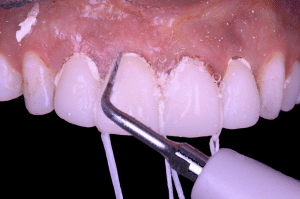

Fig 4

Dans un premier temps, les excès de ciment sont très facilement éliminés avec un insert à ultrasons fin. Mais les embrasures, malgré la finesse de l’insert restent difficilement accessibles. Quant aux espaces sous gingivaux qui ont été ouverts pour l’empreinte ne peuvent être atteints qu’à l’aveugle.